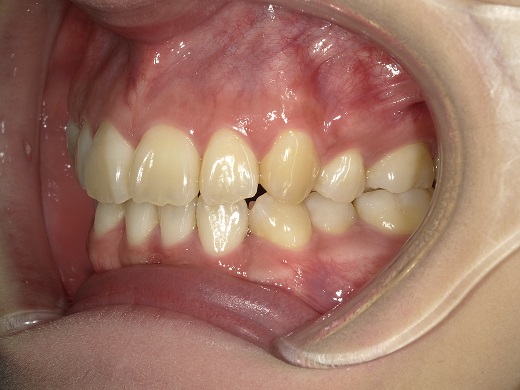

治療前左側

治療前右側